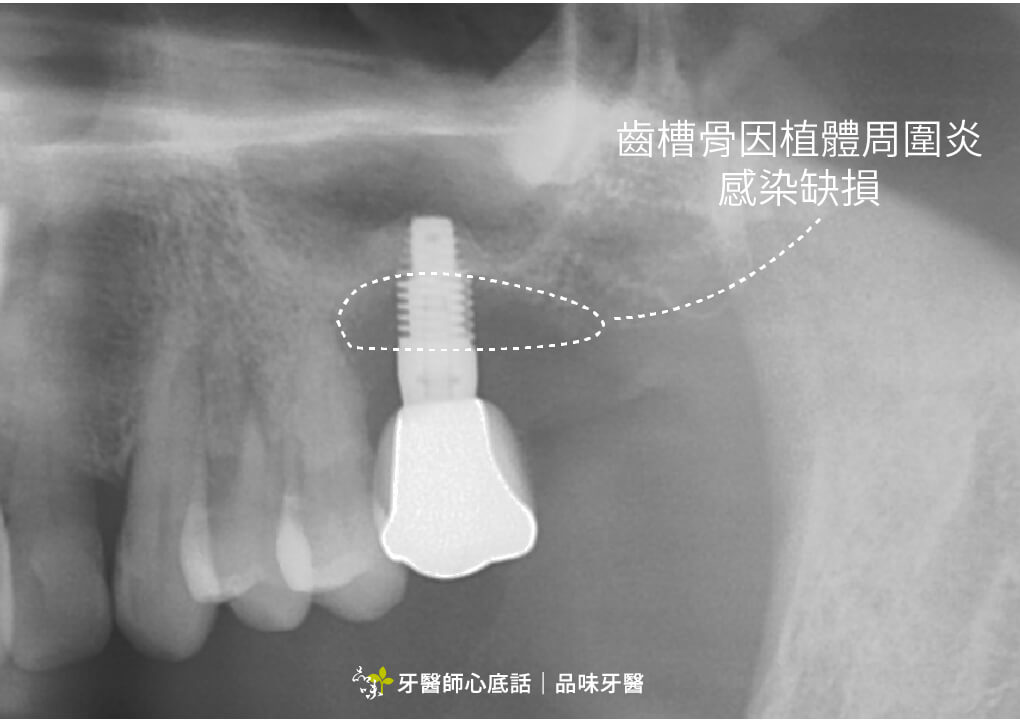

植體周圍炎

如果沒有在牙周病控制好的狀況下植牙,植體也會因此被牙周病的細菌感染,最後產生植體周圍炎(一種植牙的牙周病),最後有可能植體發炎感染,最後得移除植體。